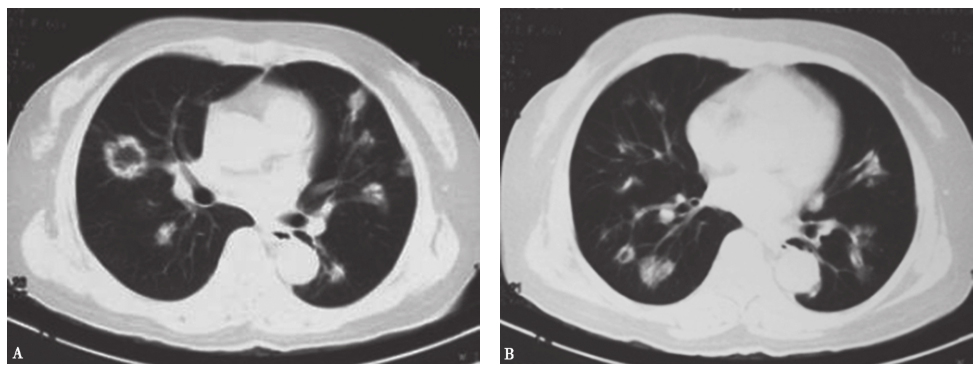

图4侵袭性肺曲霉菌病胸部CT表现

女性患者,35岁,乏力1个月,发热5天,诊断为粒细胞缺乏症合并侵袭性肺曲霉菌病。胸部CT可见双肺多发实变斑片影,多发晕征结节伴新月形空洞形成

图5肺曲霉菌感染胸部CT表现

女性患者,55岁,间断发热1个月,咳嗽1周,痰中带血1天,诊断为侵袭性肺曲霉菌病。胸部CT可见双肺多发结节影伴反晕征形成